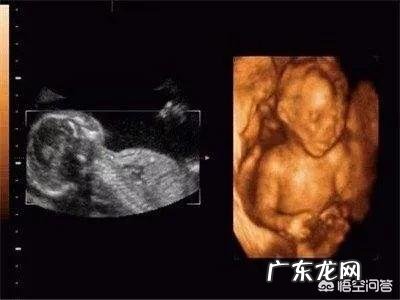

二维彩超是平面图像,三维彩超是静态立体图像,四维彩超是动态立体图像,所以二维彩超相对简单,只能检查宝宝身体上是否有大的明显的肢体畸形 。

三维彩超能够看到宝宝的整体轮廓,不仅仅是体表的畸形残缺能被看到,甚至能从里到外检查宝宝是否有器官的畸形、残缺 。但二维彩超的的局限性在于只能显示宝宝身体的某个切面,不能同步全面观察到宝宝的整体 。四维彩超是最能看清楚的,它在二维彩超、三维彩超的图像基础上,能够动态的、多角度的观察宝宝的活动情况 。

四维彩超能够显示宝宝面部、身体、四肢、内脏器官等各个部分的生长发育情况,多角度、多方位地检查身体畸形 。二维彩超和三维彩超还是图像,四维彩超是动态的影像,所以更加精准、清晰 。